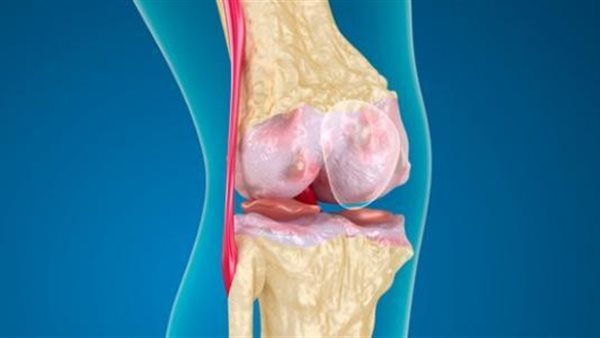

يكشف الدكتور محمد غانم، أخصائي جراحة العظام والمفاصل والكسور، عن أنواع وأعراض قطع الغضروف الهلالي للركبة، فضلا عن العلاج المناسب حسب نوع قطع الغضروف.

وعن أعراض قطع الغضروف الهلالي للركبة، يقول أخصائي العظام، أنه يتعرض الشخص لألم شديد في الركبة وخاصة عند قرار ثنيها وعند المشي، وهناك العديد من الأشخاص لا يتحركون بالشكل الجيد ويلاحظون المشكلة سريعا، ولابد من مراجعة الطبيب.

أنواع قطع الغضروف الهلالي للركبة

أما عن أنواع قطع الغضروف الهلالي للركبة، يشير طبيب العظام، إلى نوعان، الأول قطع إصابي، وهذا النوع يحدث نتيجة للحوادث أو التعرض للإصابات الرياضية، ويكون العلاج في اغلب الحالات هو التدخل الجراحي بالمنظار، إما استئصال الغضروف أو القيام بإصلاحه، وفي بعض الحالات من الممكن استخدام العلاج الطبيعي وتقوية عضلات الفخذ.

أما النوع الثاني الذي سلط الضوء عليه جراح العظام الدكتور محمد غانم، يطلق عليه «قطع تآكلي»، وهذا النوع يحدث نتيجة للتعرض للخشونة، مع تأكل مفصل الركبة، وخاصة عند كبار السن، وفي غالبية الأحيان لا يستدعي الامر تدخل جراحي، والعلاج يتم عن طريق جلسات للعلاج الطبيعي لتقوية الأربطة والعضلات حول الركبة.

ويضيف أخصائي العظام أنه عند تشخيص قطع الغضروف ومعرفة أفضل طريقة علاج، حيث ان المريض لابد من إجراء فحوصات وأشعة عادية ورنين مغناطيسي، شارحا أنه في حالة الاحساس بألم في الركبةأو في حالة شك المريض في نوع الإصابة لابد من زيارة الطبيب لمعرفة الحالة والتشخيص المناسب.